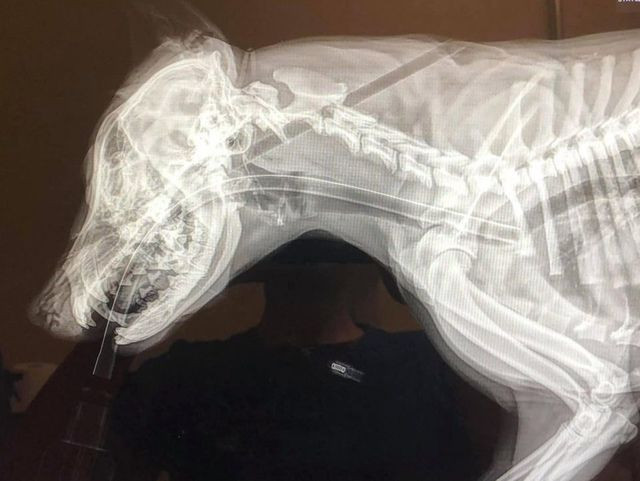

Loca 5 tháng tuổi được tìm thấy trong tình trạng hết sức thảm thương với một mũi tên xuyên qua đầu và chui ra từ đường lưng. Sau khi được phát hiện, nó lập tức được đưa đến phòng khám động vật “Paws and Claws”, nơi bác sĩ thú y giúp gỡ bỏ mũi tên và tình trạng của nó dần ổn định trở lại.

| Mũi tên đã không đi qua những cơ quan quan trọng nên Loca mới may mắn sống sót |